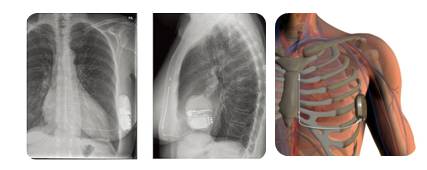

◆先植入单腔ICD,再消融第三间隔支。

术后复查心脏彩超

术后1月复查心功能好转

◆术前:NYHA III级;术后1月:接近NYHA II级。

◆术前BNP:506pg/ml;术后1月:185pg/ml